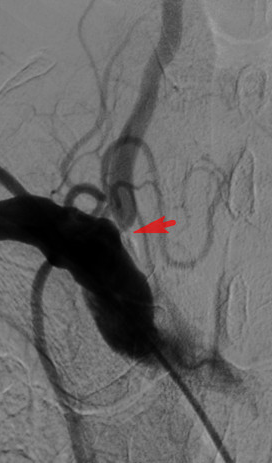

杨老伯的这次手术,也是我院首次使用药物涂层支架治疗椎动脉狭窄。术中,在贾军主任的指导下,董广宇副主任医师介入团队顺利实施椎动脉开口球囊成形及药物涂层支架置入手术,术后椎动脉开口基本恢复至正常大小。

手术非常成功。